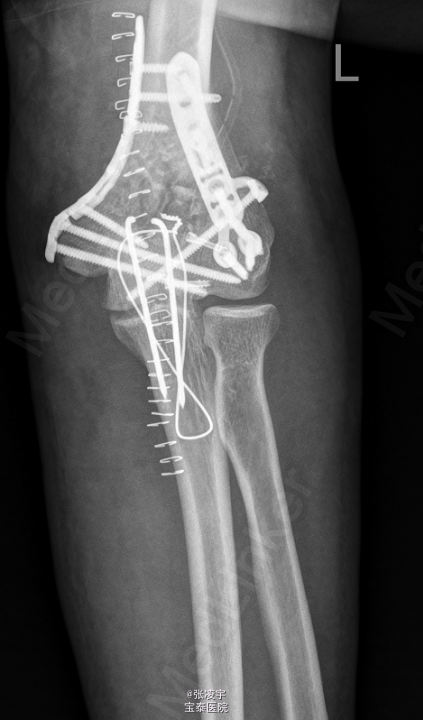

初步诊断: 1.左肱骨开放性骨折,右肘关节脱位? 行左肘关节韧带修补外固定架固定 。

术后注意功能锻炼防止粘连。